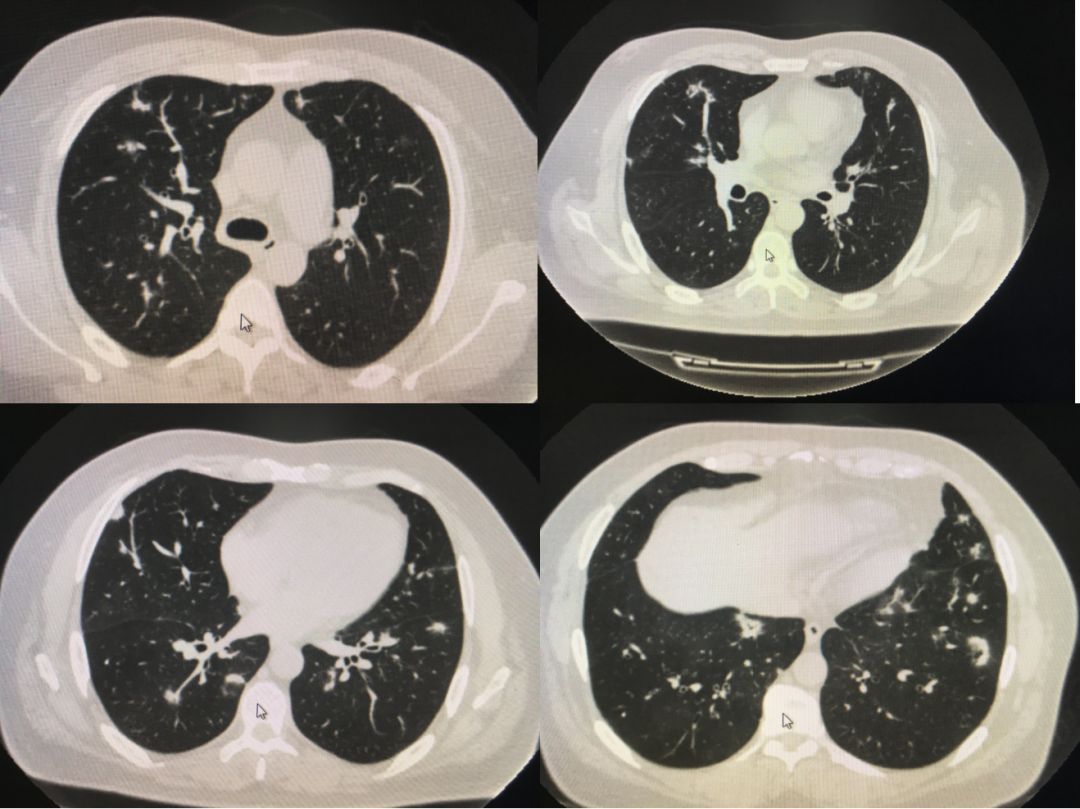

双肺多发小结节会是肺癌吗建议定期随访复查是怎么回事